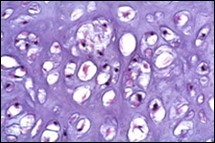

Distinction between benign cartilaginous lesions and atypical cartilaginous tumour or grade 1chondrosarcoma (ACT/CS1) can be challenging, Typically, benign cartilaginous lesions are hypo-cellular, in contrast to hyper-cellular atypical cartilaginous tumour or grade 1 chondrosarcoma 5, 6. Figure 1, Figure 2, Figure 3, Figure 4, Figure 5, Figure 6, Figure 7, Figure 8.

Figure 4.Enchondroma depicting lobules of hyaline cartilage with vacuolated cells and eccentric nuclei 12.

Figure 5.Enchondroma enunciating lobules of uniform cartilaginous cells with regular, centric nuclei and absence of mitosis 13.